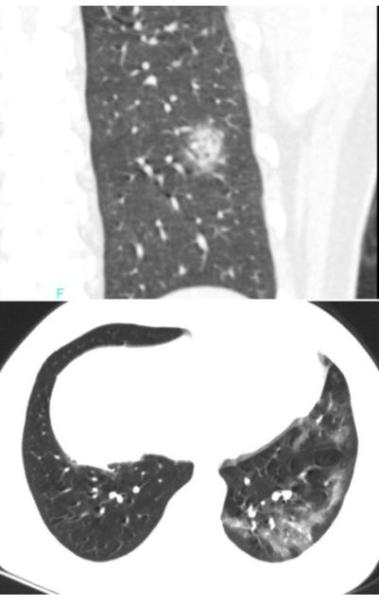

▎流感

流感,特别是甲流,也会表现为胸膜下为主的磨玻璃,但是出现的几率小于新冠肺炎。

下面的患者,就是甲流病毒性肺炎。

▎其他类型的肺炎

很多肺炎都会表现为胸膜下为主的病灶,需要结合病情具体分析。

下图是肺曲霉感染。

下图是隐球菌感染。

▎间质性肺炎

很多间质性肺炎都会表现为胸膜下为主的病灶,特别是隐源性机化性肺炎,需要结合临床表现具体分析。

下图是嗜酸细胞性肺炎。